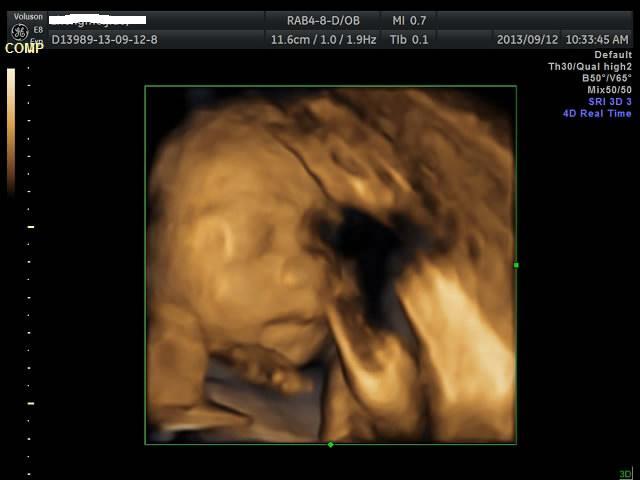

有没有能够帮我看看是千金还是帅哥的朋友?只是好奇是应该准备蓝色衣服还是应该买粉色衣服呢? 点击展开 匿名用户 2013-09-12 20:44 为您推荐: 其他回答 吓死我了... 匿名用户 2013-09-12 20:57 看不出来啊,买米黄色的吧 不论男女,都很好看 匿名用户 2013-09-12 20:57 帅哥的朋友吧,最好选粉红色的 匿名用户 2013-09-12 20:53 要怎么看才好 匿名用户 2013-09-12 20:48 千金,买粉红的 匿名用户 2013-09-12 20:47 相关问题 谁帮我看看是千金还是帅哥! 来看看我家24天的小帅哥,穿粉色衣服么么哒 张凡帅吗?很好奇听说是个帅哥,求解!!!!!!!